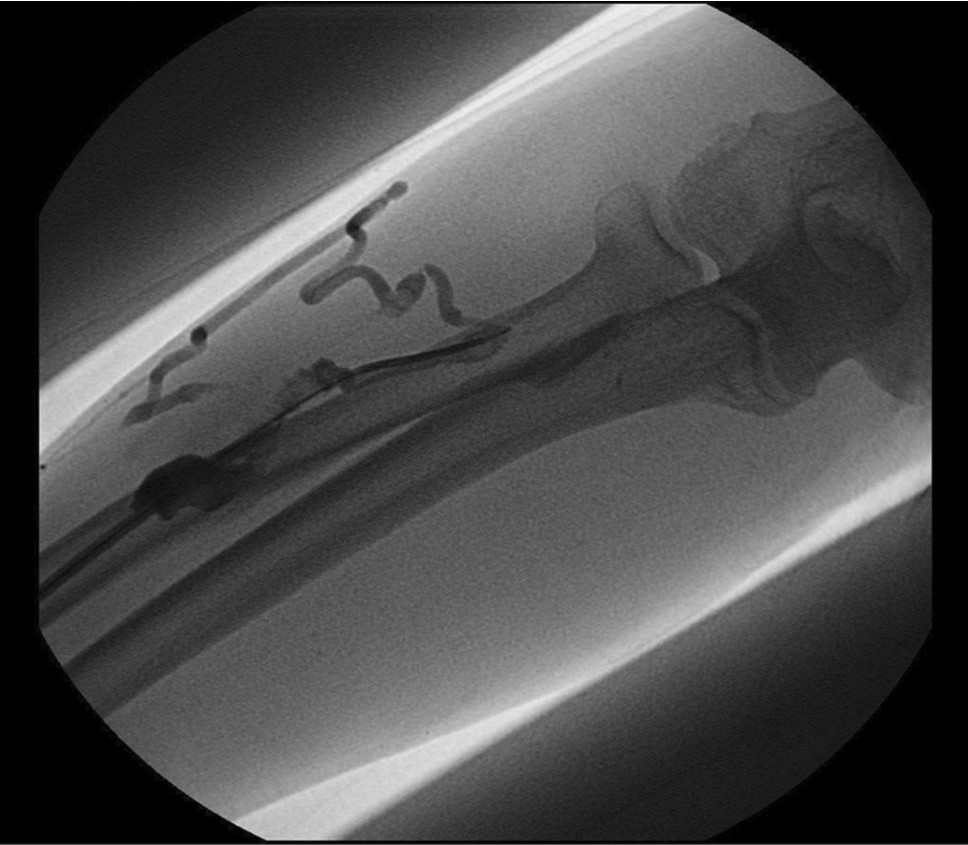

Initial shuntogram 상 total stenotic occlusion된 antecubital vein과 cephalic & basilic veins이 확인되었다(Fig. 1) 투시하에서 더 이상의 outflow vein을 확인할 수 없었으며 초음파상 1mm 크기에 가까운 흔적으로 확인되었다(Fig. 2). 7Fr, 24cm sheath(Accu-Sheath, Sung wonmedical, Korea, Cheongju) 로 폐색된 앞부위까지 전진시킨 후, 투시를 보조수단으로 하며 초음파를 main 유도 기구로 사용하여 real time으로 초음파 probe를 0.035’ J-tip & straight-tip guide wires(Terumo, Tokyo, Japan)와 5 Fr Kumpe catheter(Soft-Vu, AngioDynamics, USA, NY) 바로 위에 위치 시키면서 wire를 전진시켰다(Fig. 3). 시술 중 guide wire 가 혈관 외부로 뚫고 나가며 parenchymal injury를 유발하였다(Fig. 4A, B). 그 후 venous true lumen을 찾 angioplasty를 시행하였다(Fig. 5). 마지막 shuntogram 상 더 이상의 혈관 손상이 없이 재개통된 것을 확인하고 시술을 종료하였다(Fig. 6).

Fig. 1.

AV fistulogram : occlusion of antecubital vein with collateral flows